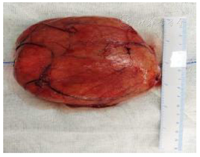

治疗方案手术切除,术前插胃管,全麻下行气管切开术+颈部肿物切除术,切口选择在皮肤肿胀较明显的左侧颈部,做"L"型切口,外上由左侧 下颌角下缘垂直向下至甲状软骨水平,水平向前至颈中线,切开皮肤、皮下组织及颈阔肌,自颈阔肌深面游离皮瓣,上至舌骨水平,下至环状软骨,沿左侧胸锁乳突肌前缘分离该肌将其牵向外侧,见淡黄色肿物(图3),质软,包膜光滑,自下而上沿包膜分离该肿物,下端达甲状腺中部,深入甲状腺被侧,上端达舌骨水平,左侧至胸锁乳突肌后缘,被侧至椎前间隙,沿该间隙于包膜外自左至右分离肿物,肿物越过中线至右侧颈动脉鞘内侧缘,术中分离并保护左 侧喉上神经、副神经、舌下神经、颈内动静脉及甲状旁腺等周围重要神经、血管,最后将肿物连带包膜完整切除,肿物切除术后手术术野(图4)。出血量不足50 ml,肿物直径约10 cm,质软,包膜完整,逐层缝合后,放 置负压引流1根,术后给予抗感染治疗,术后3 d拔引流管,术后6 d电子喉镜检查咽喉部 黏膜无充血,黏膜完整,双侧声带运动良好,拔气管套管,闭合气管切开口。术后病理(图5,图6):咽喉部巨大非典型脂肪瘤性肿瘤。